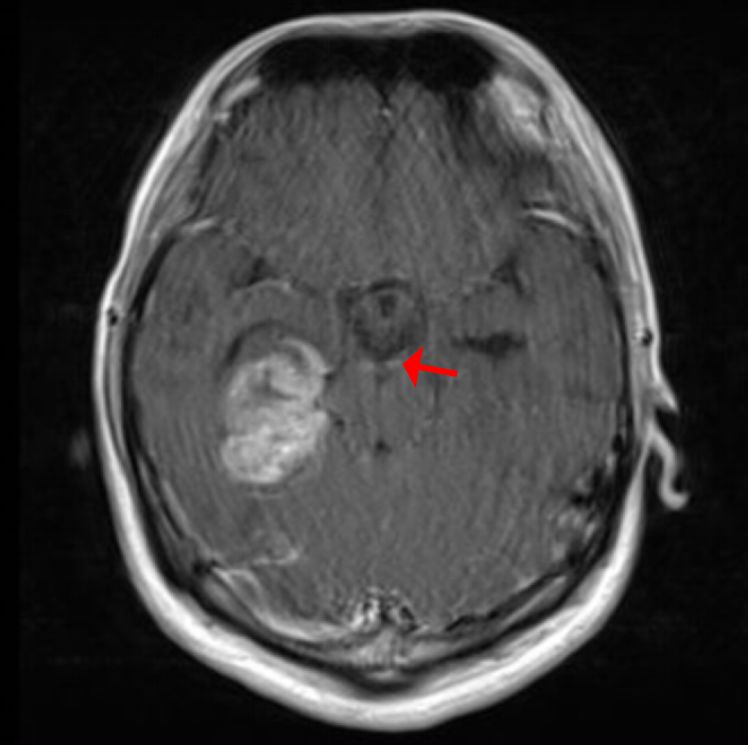

![]()

图8.术前增强头颅MRI。红色箭头示脑干周围点状增强病灶为可能的播散病灶。